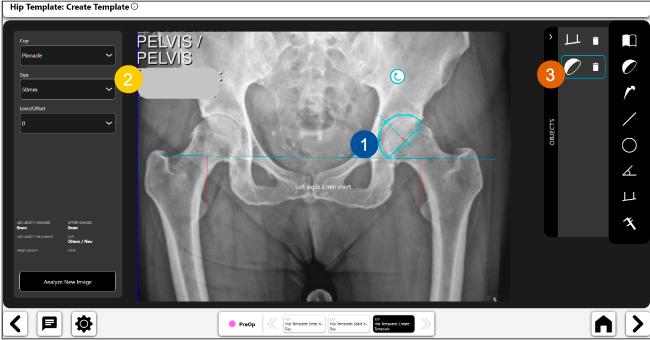

Planeación preoperatoria mediante la creación de plantillas digitales para reemplazo de cadera y análisis intraoperatorio

Beneficios de la planeación preoperatoria con Velys Hip Navigation ™

Disponibilidad de plantillas digitales de cadera.

Expediente histórico y personalizado, optimiza la planeación con el calendario de casos realizados en Velys TM y utiliza los íconos interactivos para una rápida revisión.

Espacio colaborativo: puede compartir los casos entre cirujanos y sus equipos mediante la funcionalidad de intercambio de información.

Con tecnología ONETRIAL® que calcula automáticamente el cambio en la longitud de la pierna y el desplazamiento para todas las combinaciones de implantes en una tabla fácil de leer.